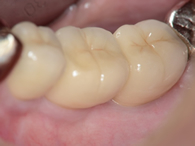

ワンデイインプラント

全く歯のない下顎にインプラントを4本埋入し、手術をしたその日のうちに固定式の歯を装着します。

骨の状態によって、1日でインプラント埋入手術から人工歯の取り付けまで行います。